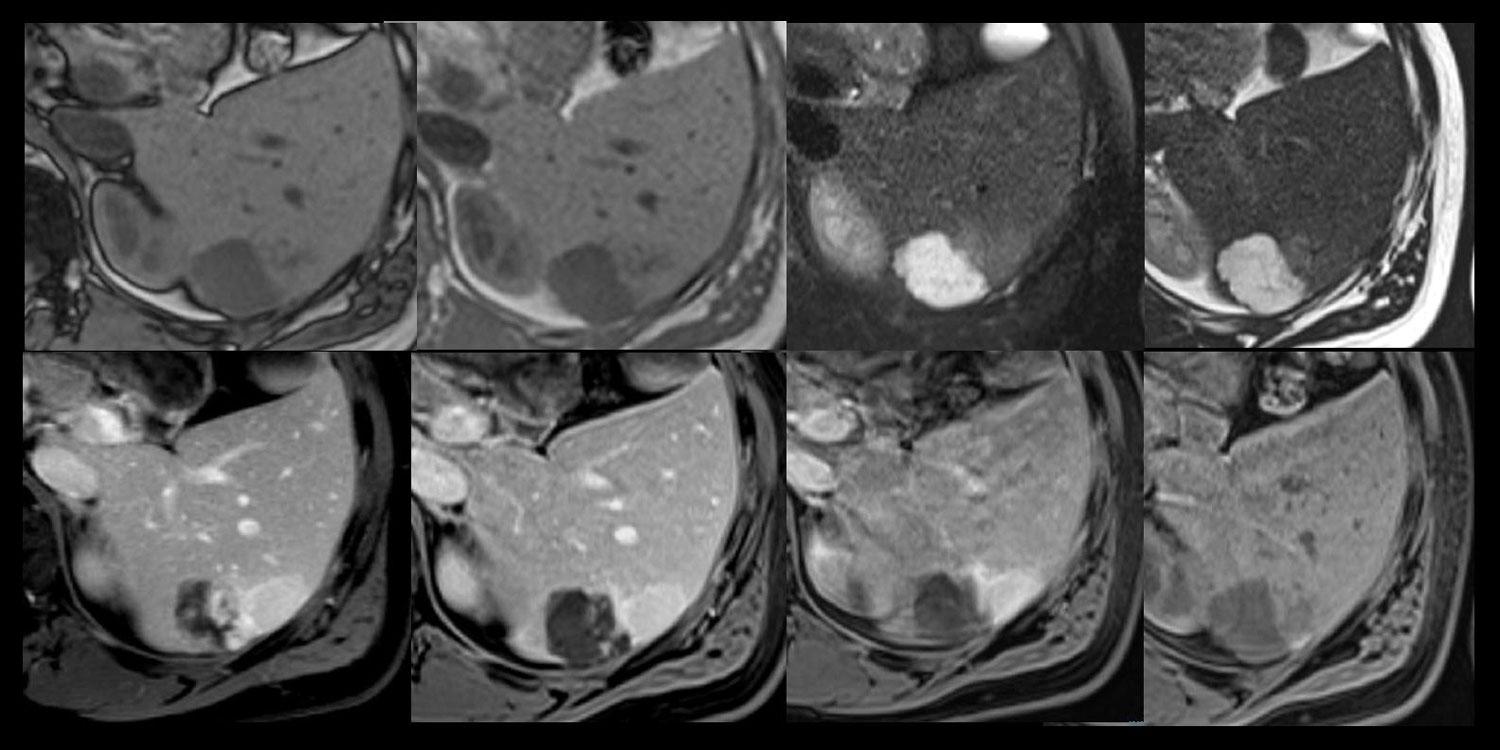

Методы динамического контрастирования печени на МРТ

Раздел: Снимки-подсказки